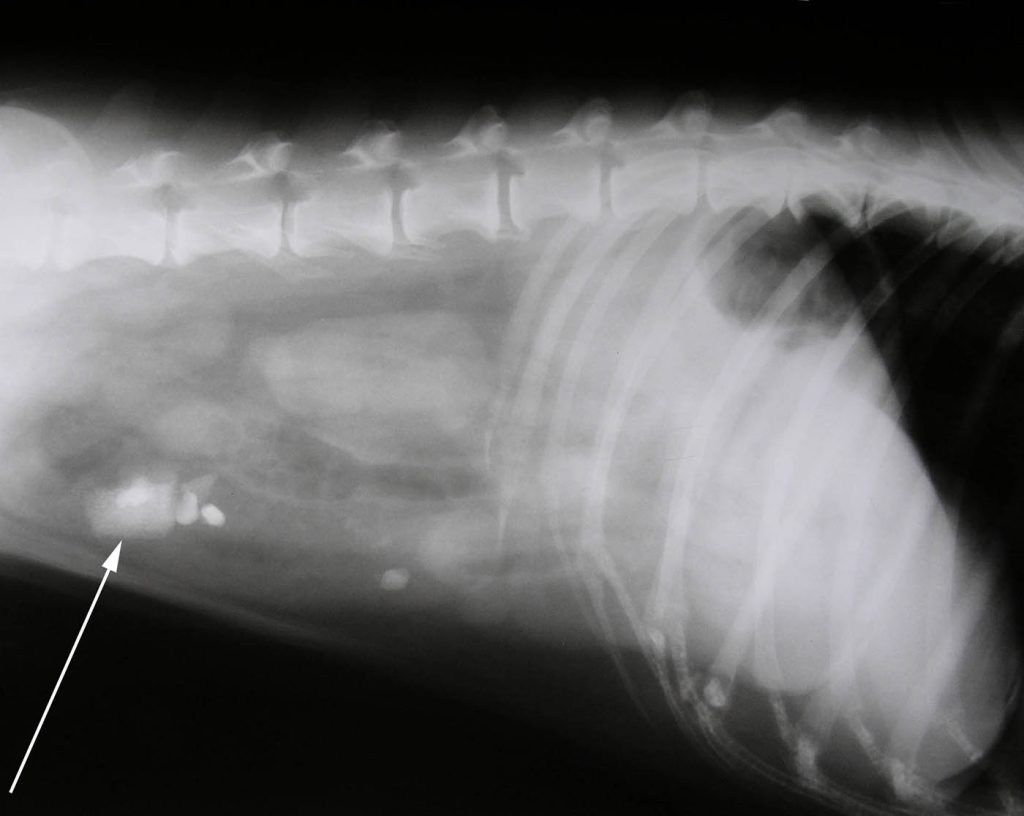

Bas ging naar huis met de nodige medicijnen en het advies aan zijn baasje om goed op vooruitgang in de gezondheid van Bas te letten. In het begin bleek Bas op te knappen, echter op vrijdag viel hij toch weer terug. Bas was weer een brakende hond. Gezien het aankomende weekend namen we geen risico’s en Bas kwam voor controle. Omdat hij nu iets gevoelig in de buik was en hij niet verder opknapte is er een röntgenfoto gemaakt. Hierop waren een aantal structuren te zien in het darmkanaal die er niet hoorde te zitten, mogelijk stenen of bot.

Dezelfde avond zijn we begonnen met opereren. Na inspectie van het maagdarmkanaal bleek de structuur die we op de röntgenfoto al hadden gezien, de dunne darm op een aantal plaatsen fiks beschadigd te hebben. Zo ernstig dat de darm op deze plaatsen wat begon te lekken en al voor een buikvliesontsteking had gezorgd.

In de darm bleken een aantal kleine steentjes te zitten, maar de structuur die het probleem gegeven had was een stuk schenkel.Mochten honden net als katten –zoals de overlevering vertelt- 9 levens hebben, dan heeft Bas met deze actie wel al zijn reservelevens verspeeld…